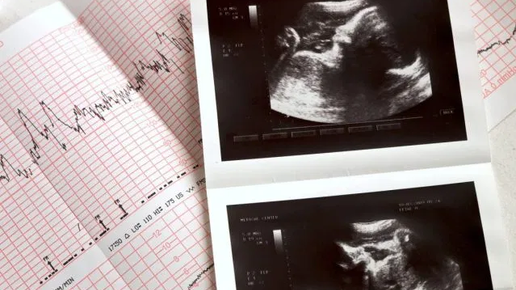

ЭхоКГ плода: что это и зачем нужно? Эхокардиография плода — это УЗ-исследование сердца малыша еще до его рождения, проводимое для того, чтобы еще до рождения выявить врожденные пороки развития сердца и вовремя принять меры во время беременности, либо своевременно провести хирургическую операцию после рождения. К сожалению, врожденные пороки сердца сегодня встречаются довольно часто, зачастую являются причиной гибели малыша после его рождения. Пороки сердца все еще пропускаются при скрининговом...

Как делают КТГ плода при беременности?

Гинеколог определяет внешние показатели у беременной женщины каждый прием. КТГ плода при беременности, наоборот, оценивает внутриутробное состояние ребенка. Для исследования используют специальный ультразвуковой датчик, который улавливает сердцебиение малыша...